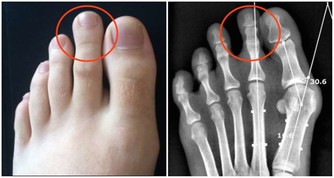

西醫的檢查是病變的結果檢查,只有到了身體通過量變的積累達到了質變時候才能檢查出來。這是為什麼有的人心悶、頭痛全身不舒服,到醫院卻什麼也檢查不出來的道理。這就是為什麼癌症只有到了晚期才能檢查出來的原因,因為早期不叫癌症,早期就叫高血壓、糖尿病、腎炎、乙肝、風濕、哮喘、附件炎等等。"